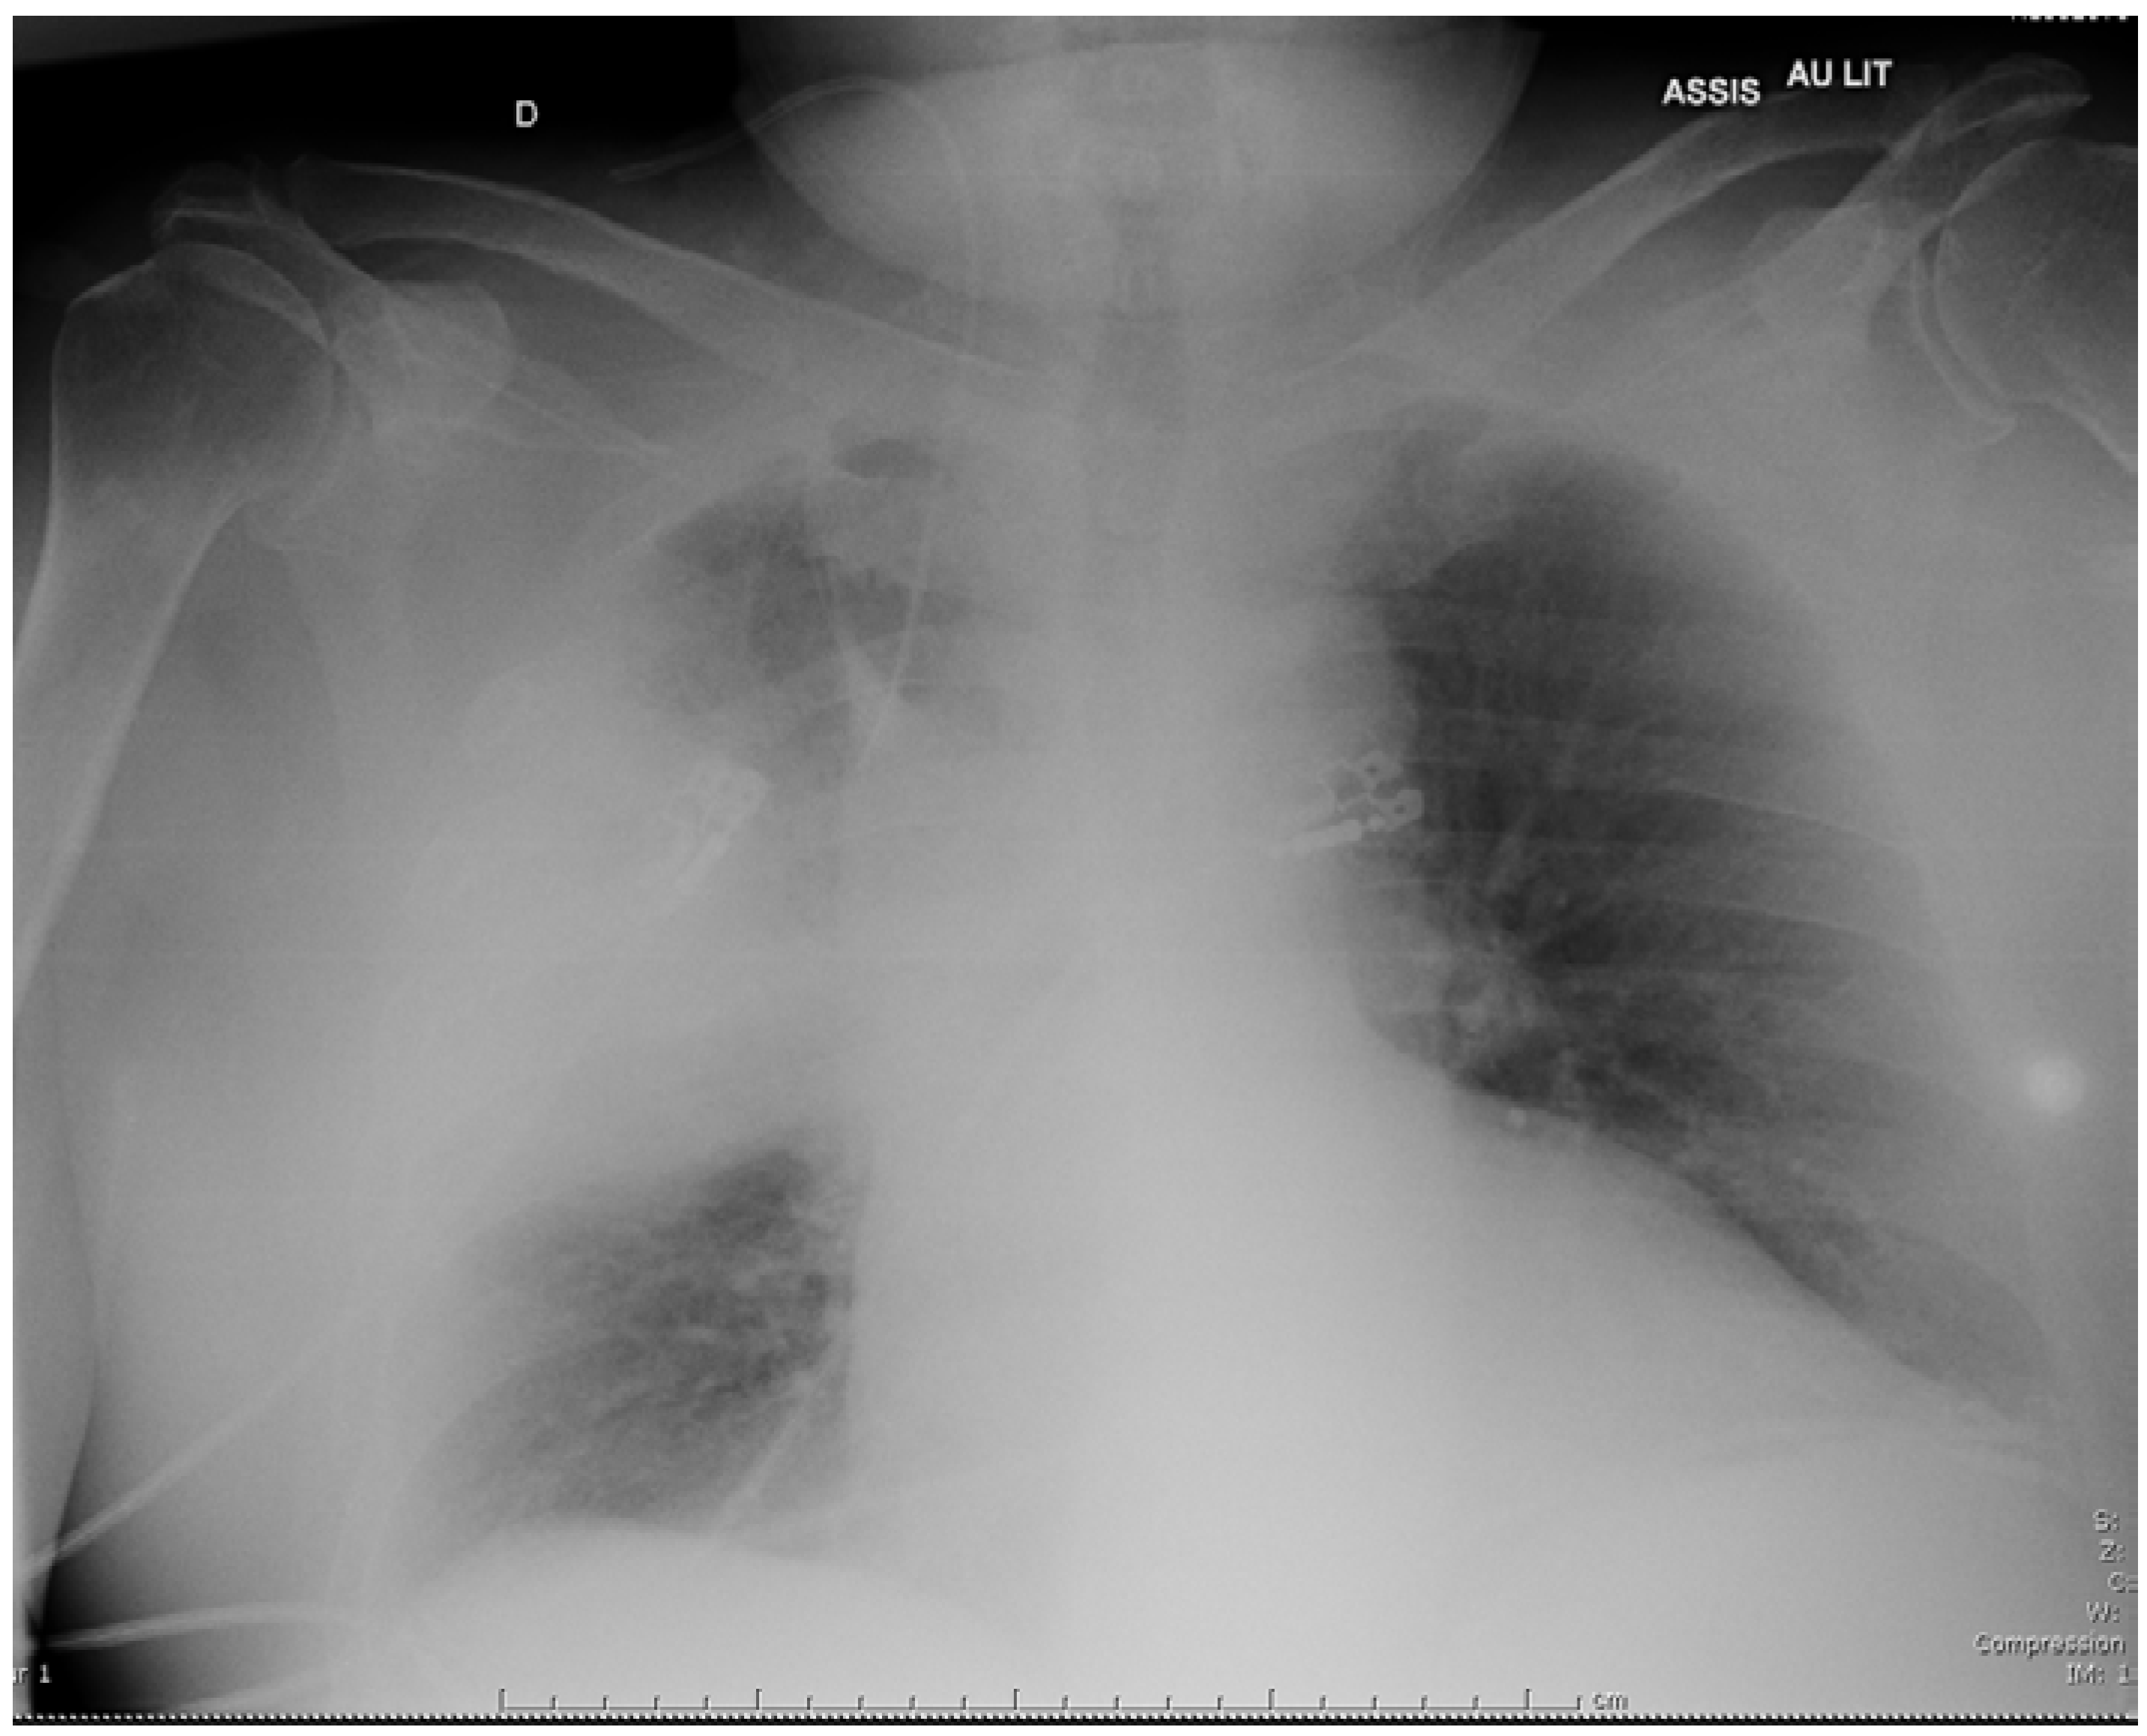

A 69-year-old man presented in November 2018 with a 3-day history of cough and fever. He reported significant tobacco consumption, type 2 diabetes, obstructive sleep apnea (OSA) and rheumatoid arthritis (RA) treated with successive tumor necrosis factor-alpha inhibitors since 2004. His immunosuppressive therapy had been strengthened with high-dose corticosteroids in August 2018 because the RA had relapsed, and etanercept had just been replaced by abatacept (an inhibitor of the cytotoxic T lymphocyte-associated antigen-4 receptors) few days prior to admission. The first evaluation revealed: temperature of 37.9 °C, blood pressure of 126/69 mmHg, respiratory rate of 32/min, and oxygen saturation of 95% on 3L/min of O2. He was alert but complained of cough and dyspnea. The chest examination mainly revealed crackles in the right field. Initial lab work showed: hemoglobin 12.8 g/dL, WBC count 9,600 /µL, platelet count 178,000 /µL, creatinine level 22.3 mg/L, C-reactive protein 514 mg/L, and procalcitonin 4.9 ng/mL. On room air arterial blood gas showed pH of 7.50, O2 pressure of 53 mmHg, and CO2 pressure of 34 mmHg. Chest X-ray demonstrated alveolar infiltrates in the middle part of the right lung (Figure 1). The patient received intravenous (i.v.) cefotaxime, 2 g every 8 h, plus i.v. levofloxacin, 500 mg daily, as empirical therapy, then was admitted to the intensive care unit because he required non-invasive ventilation.

Figure 1.

Chest X-ray on admission showing a right consolidation in the right lung.